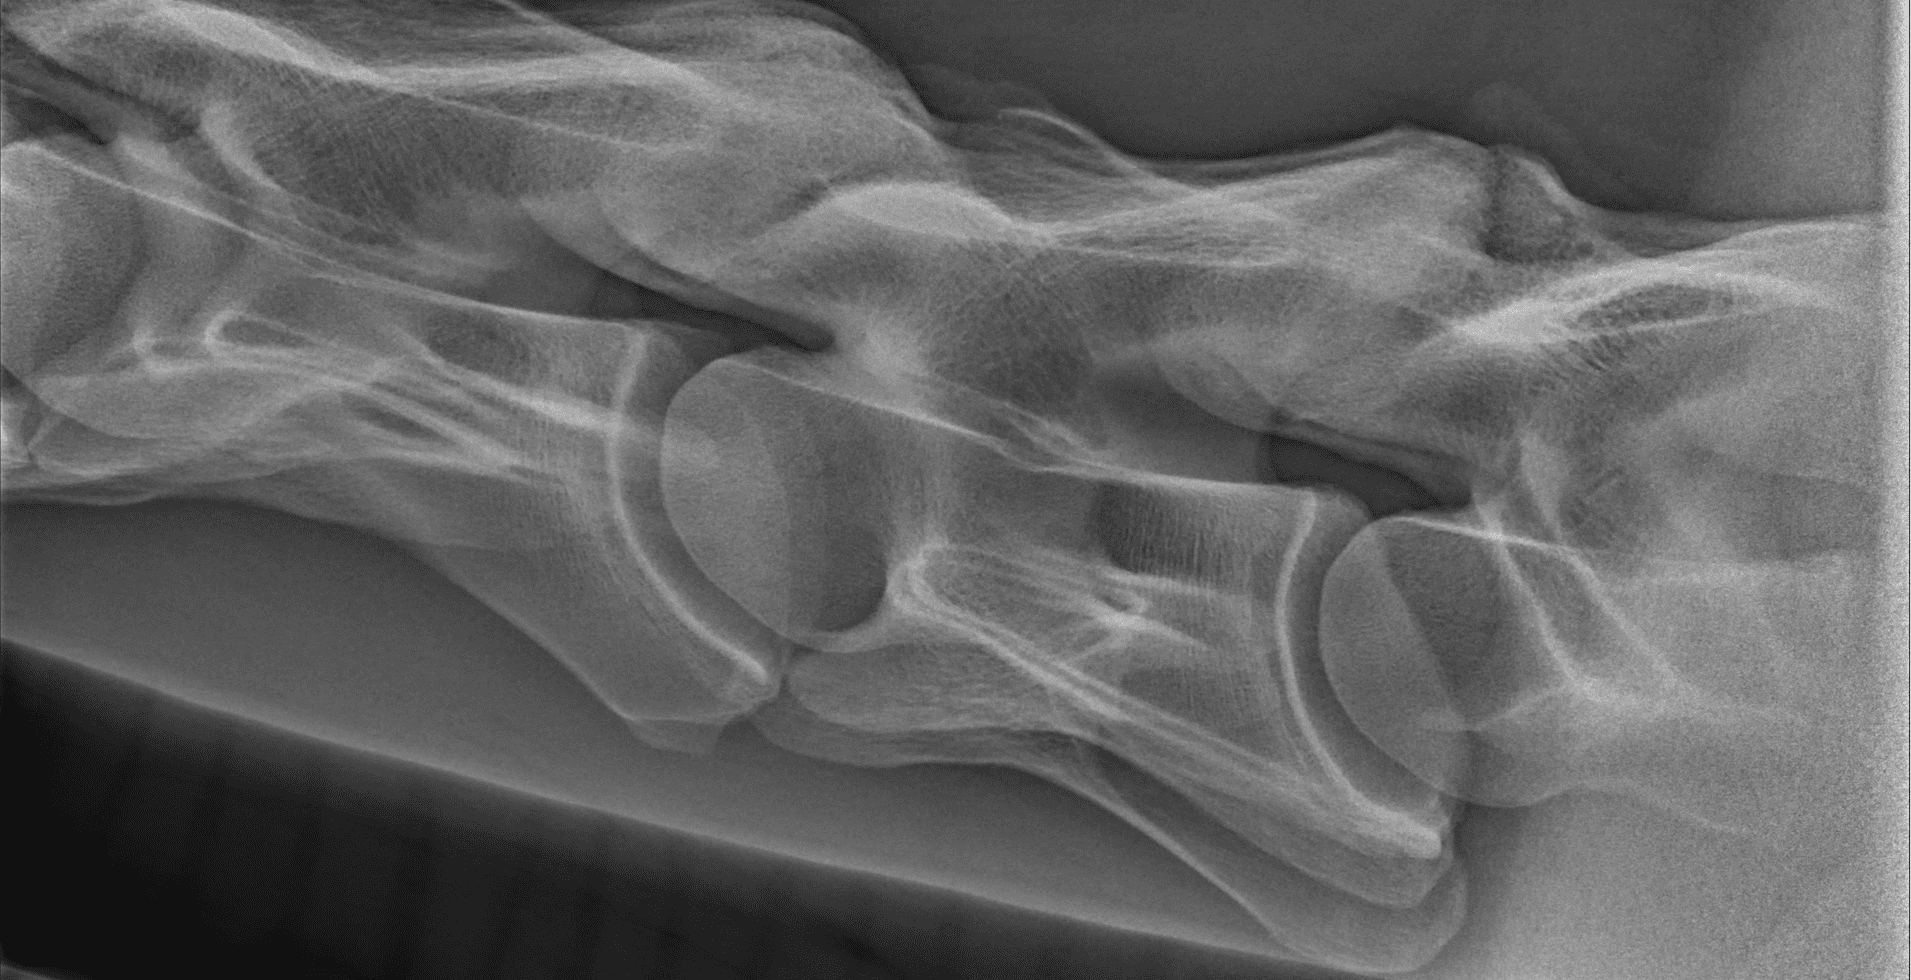

Een röntgenapparaat kan met behulp van röntgenstralen foto’s maken van de binnenkant van het lichaam. Vanwege hun doordringende vermogen kan met name het skelet op die manier goed bekeken worden, maar ook andere organen zoals de longen. Het röntgenonderzoek heeft een vlucht genomen met de introductie van de digitale röntgen. Beelden kunnen worden vergroot, contrasten groter of kleiner gemaakt en informatie kan via de computer makkelijk en snel worden uitgewisseld.

Bij onderzoek naar een stoornis aan het bewegingsapparaat (orthopedisch onderzoek) wordt röntgen intensief gebruikt. Röntgenonderzoek laat veranderingen zien zoals kreupelheid, fracturen, botontstekingen en standsafwijkingen. Ook aanhechtingsproblemen van pezen en banden met botafwijkingen zijn in beeld te brengen. Daarnaast wordt röntgenonderzoek gebruikt bij problemen aan het hoofd en het gebit. Bij onderzoek naar problemen aan de luchtwegen kunnen röntgenfoto’s gebruikt worden voor het stellen van een diagnose. Voor een röntgenonderzoek wordt het paard onder lichte verdoving gebracht, zodat deze keurig stil staat en minder onder de indruk is van alle apparatuur. Om problemen in beeld te brengen zijn vaak meerdere röntgenfoto’s van dezelfde locatie noodzakelijk. Eén foto zegt meestal onvoldoende. Bij de keuring van het paard wordt een min of meer standaard set gemaakt. Ook daarbij worden van diverse gewrichten meerdere röntgenfoto’s uit verschillende richtingen gemaakt.